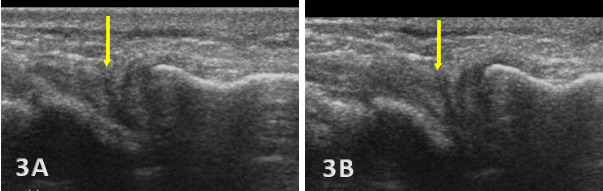

Hypoechoic or anechoic cleft seen within the normal fibrillar pattern of a normal TFCC.

Irregular or disrupted margins of the articular disk.

Thinning or fissuring of the TFCC indicates a partial-thickness tear.

Abnormal thickness of the TFCC, such as thinning (degeneration) or thickening (edema or chronic overuse), may be seen as pathology.

A complete disruption of the continuity of fibers of ligaments or the disk with fluid extending into the joint would indicate a complete full-thickness tear of the TFCC.